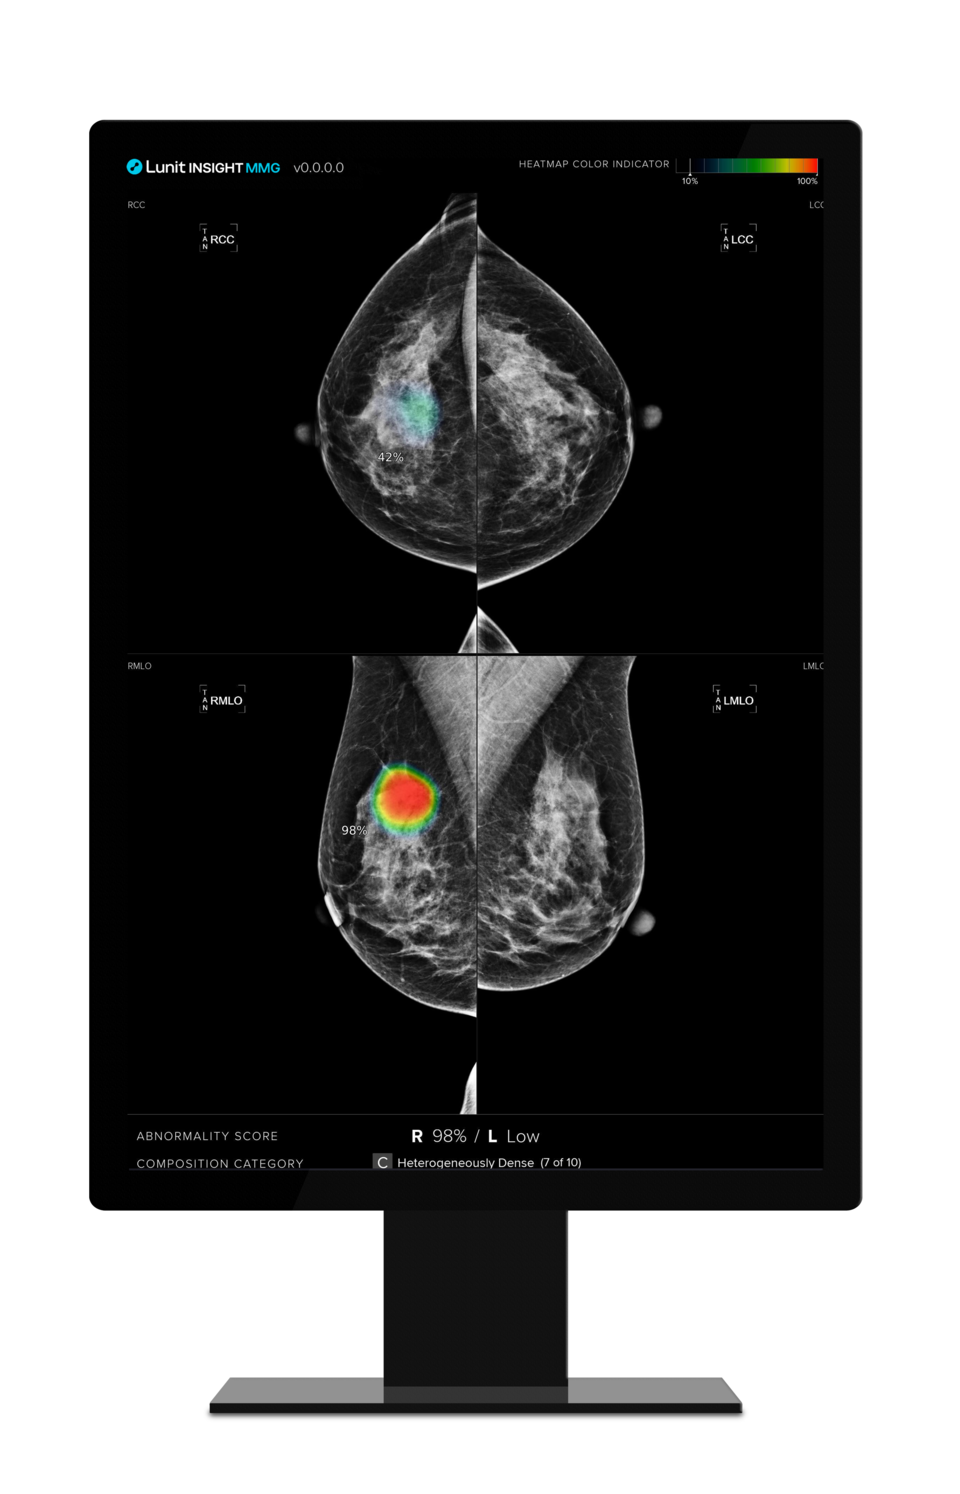

의료 인공지능(AI) 기업 루닛(대표 서범석)은 유방촬영술 AI 영상분석 솔루션 '루닛 인사이트 MMG'의 암 진단 능력이 1차 판독 전문의(First-Reading Breast Radiologist)와 유사하거나 더 나은 수준이라는 연구 결과가 유럽 영상의학 학술지 'European Radiology(IF 7.0)'에 게재됐다고 23일 밝혔다.

현재 유럽에서는 유방암 검진 시 영상의학과 전문의 두 명이 판독을 진행(Double Reading)하도록 권고하는 가운데, 연구팀은 루닛 AI 솔루션과 1차 영상의학 전문의의 결과를 비교해 AI의 암 진단 능력을 평가했다.

루닛 AI 솔루션은 1차 판독 전문의들의 평균 민감도(Sensitivity, 암 환자를 암 환자로 판정할 확률)를 임계값으로 적용한 AI 모델(이하 AIsens 모델)과 1차 판독 전문의들의 평균 특이도(Specificity, 암 환자가 아닌 일반인을 암이 아닌 것으로 판정할 확률)를 임계값으로 적용한 AI 모델(AIspec 모델)로 사례들을 판독했다. 임계값을 초과하는 경우 암 추가 검사를 위해 환자를 다시 소환하는 '리콜(Recall)' 대상으로 분류했다.

그 결과 AIsens 모델은 1차 판독 전문의보다 특이도(97.5% 대 97.7%)와 양성예측값(17.5% 대 18.7%)이 약간 낮았으나, 리콜률은 3.0% 대 2.8%로 더 높았다. 이는 AI가 유방 이상 징후를 거의 놓치지 않으며, 더 많은 잠재적 암 사례를 식별할 수 있음을 의미한다고 회사는 설명했다.

AIspec 모델은 전문의와 유사한 정확도 결과를 보였다. AIsens, AIspec 모델 모두 전문의보다 암을 적게 발견했지만(AIsens 1166건, AIspec 1156건, 전문의 1252건), 유방촬영술 검사 주기 사이에 발생한 간격암(Interval cancer)은 약 3~4배 더 발견했으며(AIsens 126건, AIspec 117건, 전문의 39건), 유방암 및 다른 암종도 발견했다.

이번 연구는 이중 판독 과정에서 AI가 전문의의 1차 판독을 보조하거나 대체할 가능성을 보여주며, AI의 적용이 암 검출률을 더욱 높일 수 있음을 시사한다.